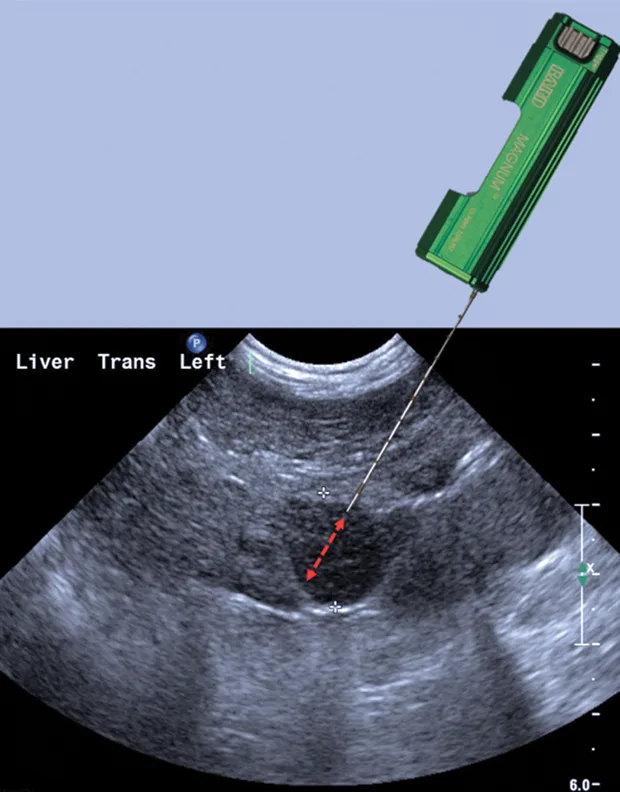

Spring-loaded needle biopsy devices are preferred over manual devices because the samples provided are more consistent and larger. The spring-loaded needle biopsy devices come in 2 types: semiautomated and fully automated (Figure 1; see Image Gallery). The semiautomated device is spring-loaded to drive the cutting cannula over the manually preplaced inner stylet. With a fully automated device, a spring-loaded gun is used to drive both the inner stylet and outer cutting cannula in rapid succession (Figures 1 and 2; see Image Gallery). Usually 14-, 16-, or 18-gauge biopsy core needles are used for liver biopsy. Choice is partially dependent on the overall animal size, lesion size, pathology service, and type of test (eg, histopathology, culture and susceptibility, copper levels) for which the biopsy sample is being used.

Larger-gauge biopsy devices (14-gauge) increase the risk for hemorrhage, especially with passage of the needle deep into the liver. However, a major limitation of needle biopsies is the size of the sample retrieved, so a balance between patient safety and sample size needs to be considered.4,5 Biopsy needles vary in actual length and in length of the biopsy stylet for the core liver tissue to be obtained (typically 12, 15, or 20 mm long). Semiautomated devices tend to have a fixed stylet length, whereas biopsy length can be altered with some of the fully automated devices. The fully automated biopsy device (Figure 3A; see Image Gallery) advances into the tissue a set distance depending on the length of the inner stylet that receives the tissue. This distance should be taken into account before firing the device to ensure that a proper specimen is likely to be collected and that non-target tissues are not sampled. For the semiautomated biopsy device, the inner (receiving) stylet is manually advanced prior to firing the outer cutting portion of the biopsy device (Figure 3B; see Image Gallery). On average, 3 to 4 quality samples are taken and placed in formalin for routine histopathology. Other types of sample handling will be required for determining copper content or specific types of tissue testing, as well as for culture and susceptibility testing. The clinician should be prepared ahead of time for the type of fixation or sample handling procedures so that the tissue sample is fresh and handled in an appropriate fashion.

FIGURE 1A

Fully automated Bard biopsy device (A; bardbiopsy.com) in which the disposable biopsy needle is placed into the biopsy device at the time of the biopsy. A semi-automated Bard biopsy device (B) in which the spring-loaded trigger will only engage the outer sleeve in a cutting fashion over the receiving tissue stylet that has already been manually advanced into the tissue.